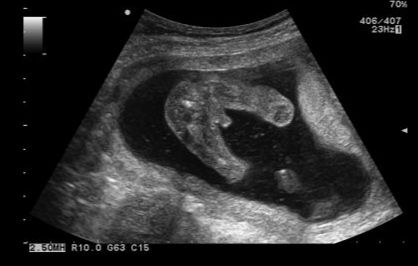

Привет пузатики! Напишу обо всём по чуть- чуть, чтоб не забылось)) В эту беременность все происходит немного по другому что-ли. Первая Б в 23 года, вторая в 30 лет. Первая естественно протекала идеально,я летала почти всю беременность, ну за исключением уже недель после 35 где-то, там пуз мешал уже. Сейчас же, все немного сложнее, Б началась с сохранения,6-8 недель, потом старалась беречься и поменьше скакать, боялась что отслойка опять может быть, но слава Богу все хорошо😊 шевеления в этот раз начала чувствовать с 16 недель, начались они с нежных пиночков, которые сейчас уже очень хорошо чувствую даже рукой. А в первую Б начались они в 15 недель с перекатов и копошений, пиночки были позднее. Из неприятного: появился варикоз наружных половых органов😬, если я на ногах или за рулём больше часа, то всё, боль и отёк "там" обеспечены до следующего дня... Как же это неприятно, когда "там" у тебя болит, что аж с боку на бок не хочется переворачиваться, ходить, вобще молчу😔 но я готова ко всему, лишь бы с малышом всё было хорошо))) На первом скрининге в обе Б рассмотрели мальчика, в 17 недель подтвердили и дали фото причинного места)) мы счастливы💕 думаем над именем, пока споров в этом вопросе нет. Из различий ещё: в 1 Б принимала только витамины и иногда папаверин от тонуса, а в эту у меня прогестероновая недостаточность и я на Утрожестане, уже снизили до 400 всутки. Хожу мерить шейку каждые 10 дней, т.к. есть подозрения, что может укоротиться - в родах была сильно травмирована. Надеюсь, что нас это обойдет стороной. Пузяш растёт с одинаковой скоростью в обе беременности)) начал появляться настоящий беременный животик на 16 неделе🥰 Из покупок всё уже есть, осталось мелочь докупить, типа пустышки, бутылочки. Наслаждаемся беременностью и никуда не спешим))

По фото это вид снизу или сверху, не разберусь))